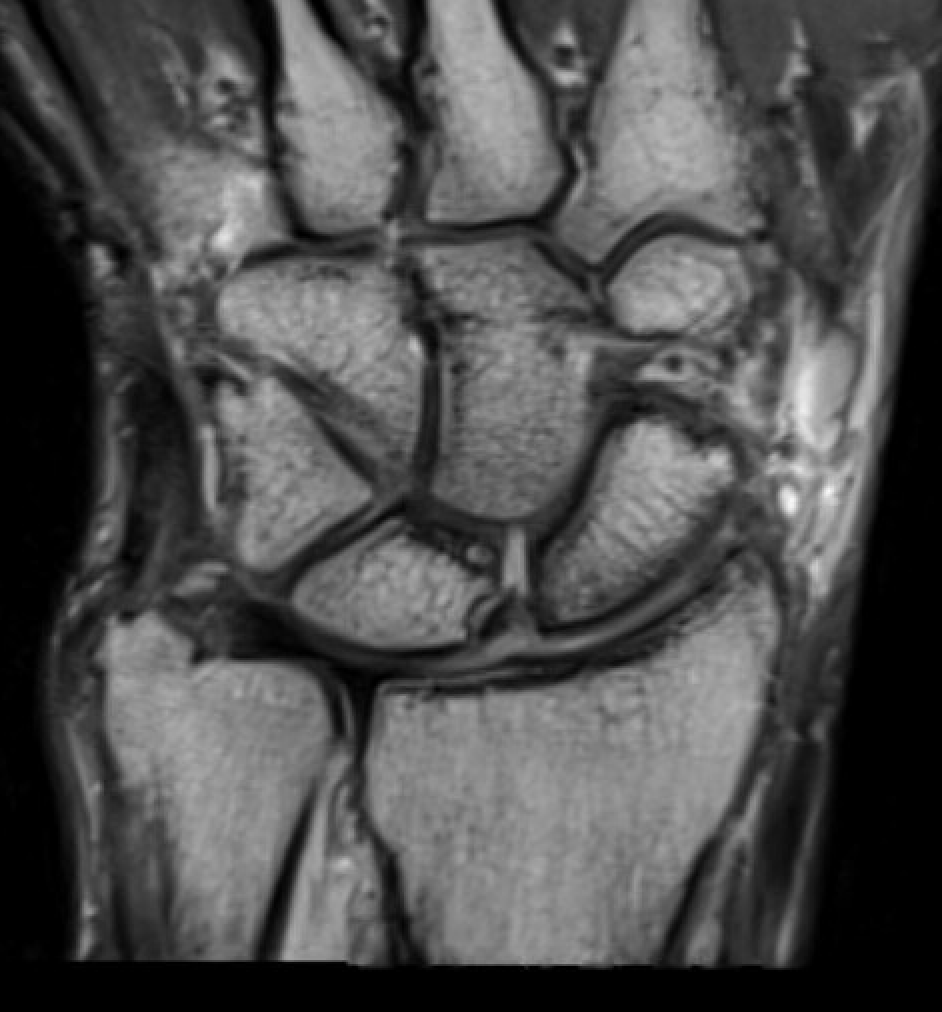

CT

MRI

SL ligament injury with minimal disassociation / SL separation / dynamic instability

SL ligament injury with SL separation and static instability

Increased scapholunate angle